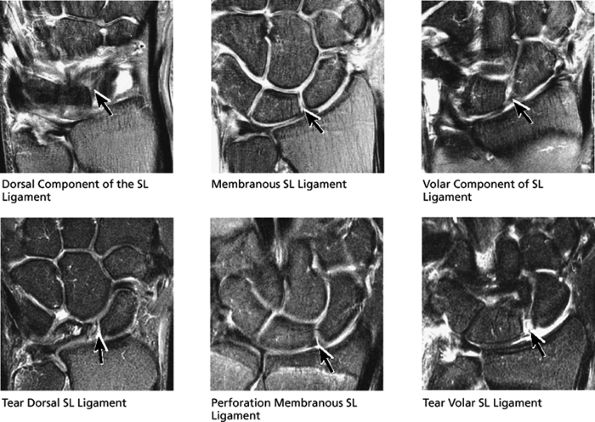

The scapholunate ligament is triangular on coronal section and is peripherally attached at the scapholunate interval. The inner apex of the triangular ligament is not attached to bone and is free within the scapholunate joint (Fig. 10.74).52

-

The dorsal fibers of the scapholunate ligament are oriented transversely, or perpendicular to the joint, and form a thick bundle. The dorsal portion of the scapho-lunate ligament is considered to be the most important component in maintaining carpal stability.

The membranous scapholunate ligament fibers course peripherally and obliquely from the scaphoid downward to the lunate. The membranous scapholunate ligament fibers attach to both bone and articular cartilage, whereas the dorsal and volar portions of the scapholunate ligament attach directly to bone.

The volar scapholunate ligament fibers course obliquely between the volar aspects of the lunate and scaphoid.

However, a fluid-filled gap interposed between the membranous scapholunate ligament and the cartilage or bones should be interpreted as a perforation or detachment. Such membranous scapholunate ligament perforations and detachments are more common with advancing age (similar to tears of the TFC central disc), and in isolation may not necessarily result in carpal instability or significant symptoms. The volar-most images demonstrate the volar scapholunate ligament, which courses obliquely and attaches to bone on either side of the ligament. Tears of the volar and radial aspects of the scapholunate ligament suspected in the coronal plane can be confirmed in the axial plane. After identifying a scapholunate ligament tear, the scapholunate interval is assessed for widening, reactive bone marrow changes on either side of the scapholunate articulation, and bony or cartilaginous avulsions at the site of tearing or detachment. In addition, in the setting of scapholunate ligament tears, associated patterns of carpal instability, such as dorsal intercalated segment instability (DISI) pattern, can be identified on corresponding sagittal images.